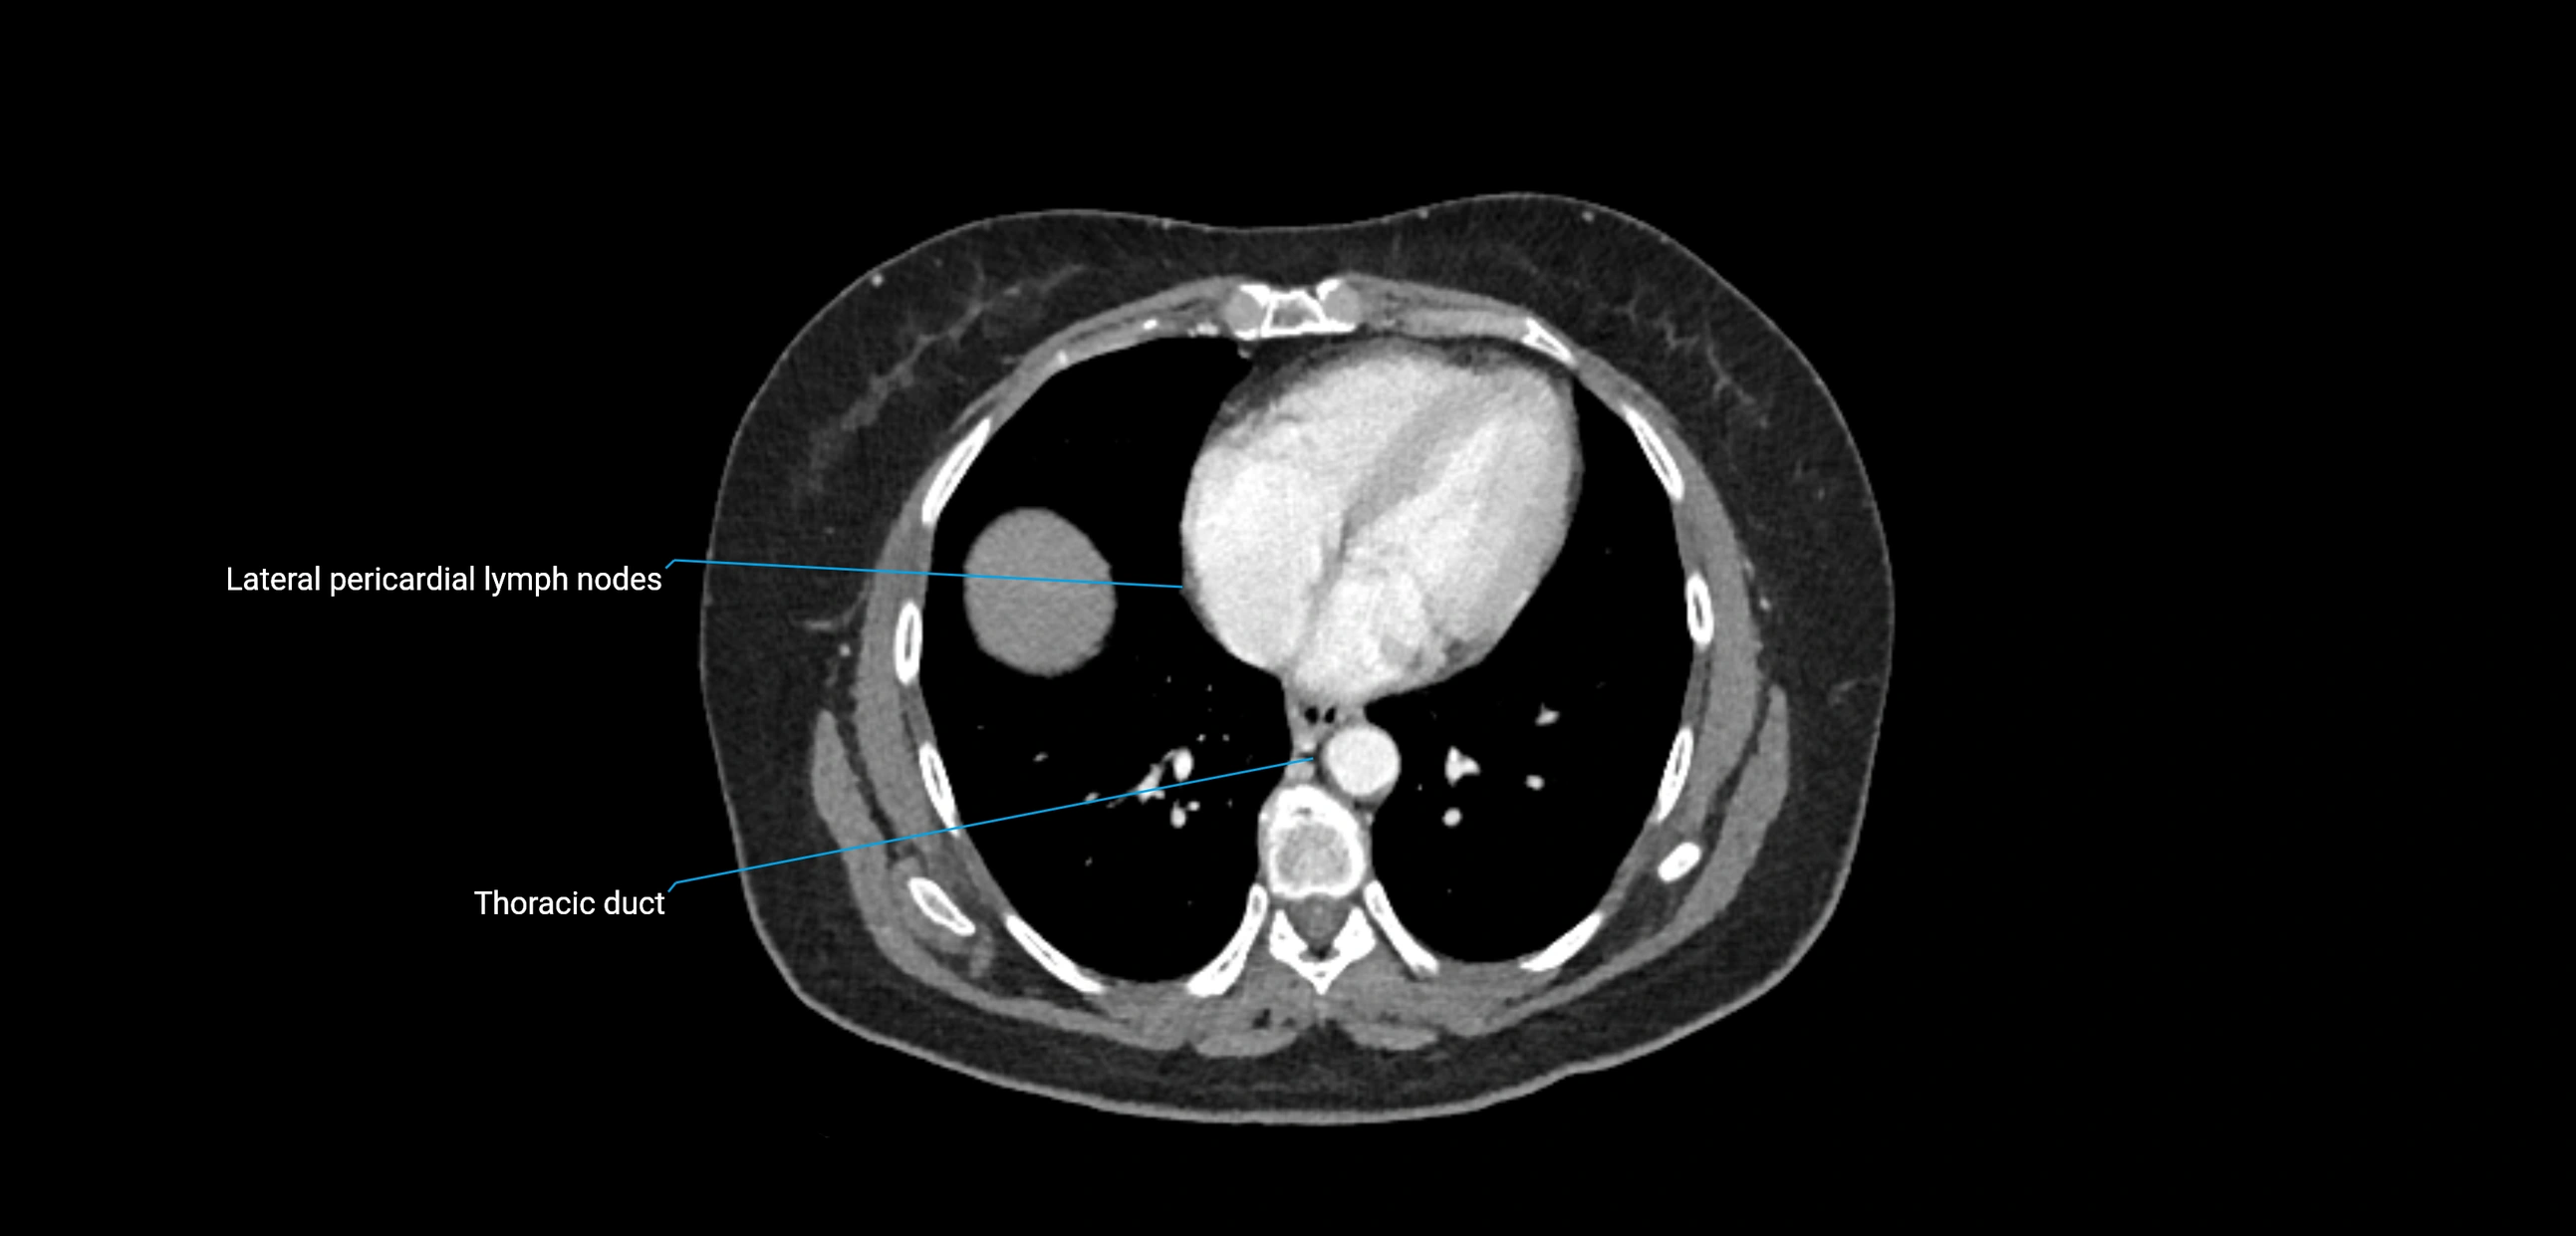

CT image

image